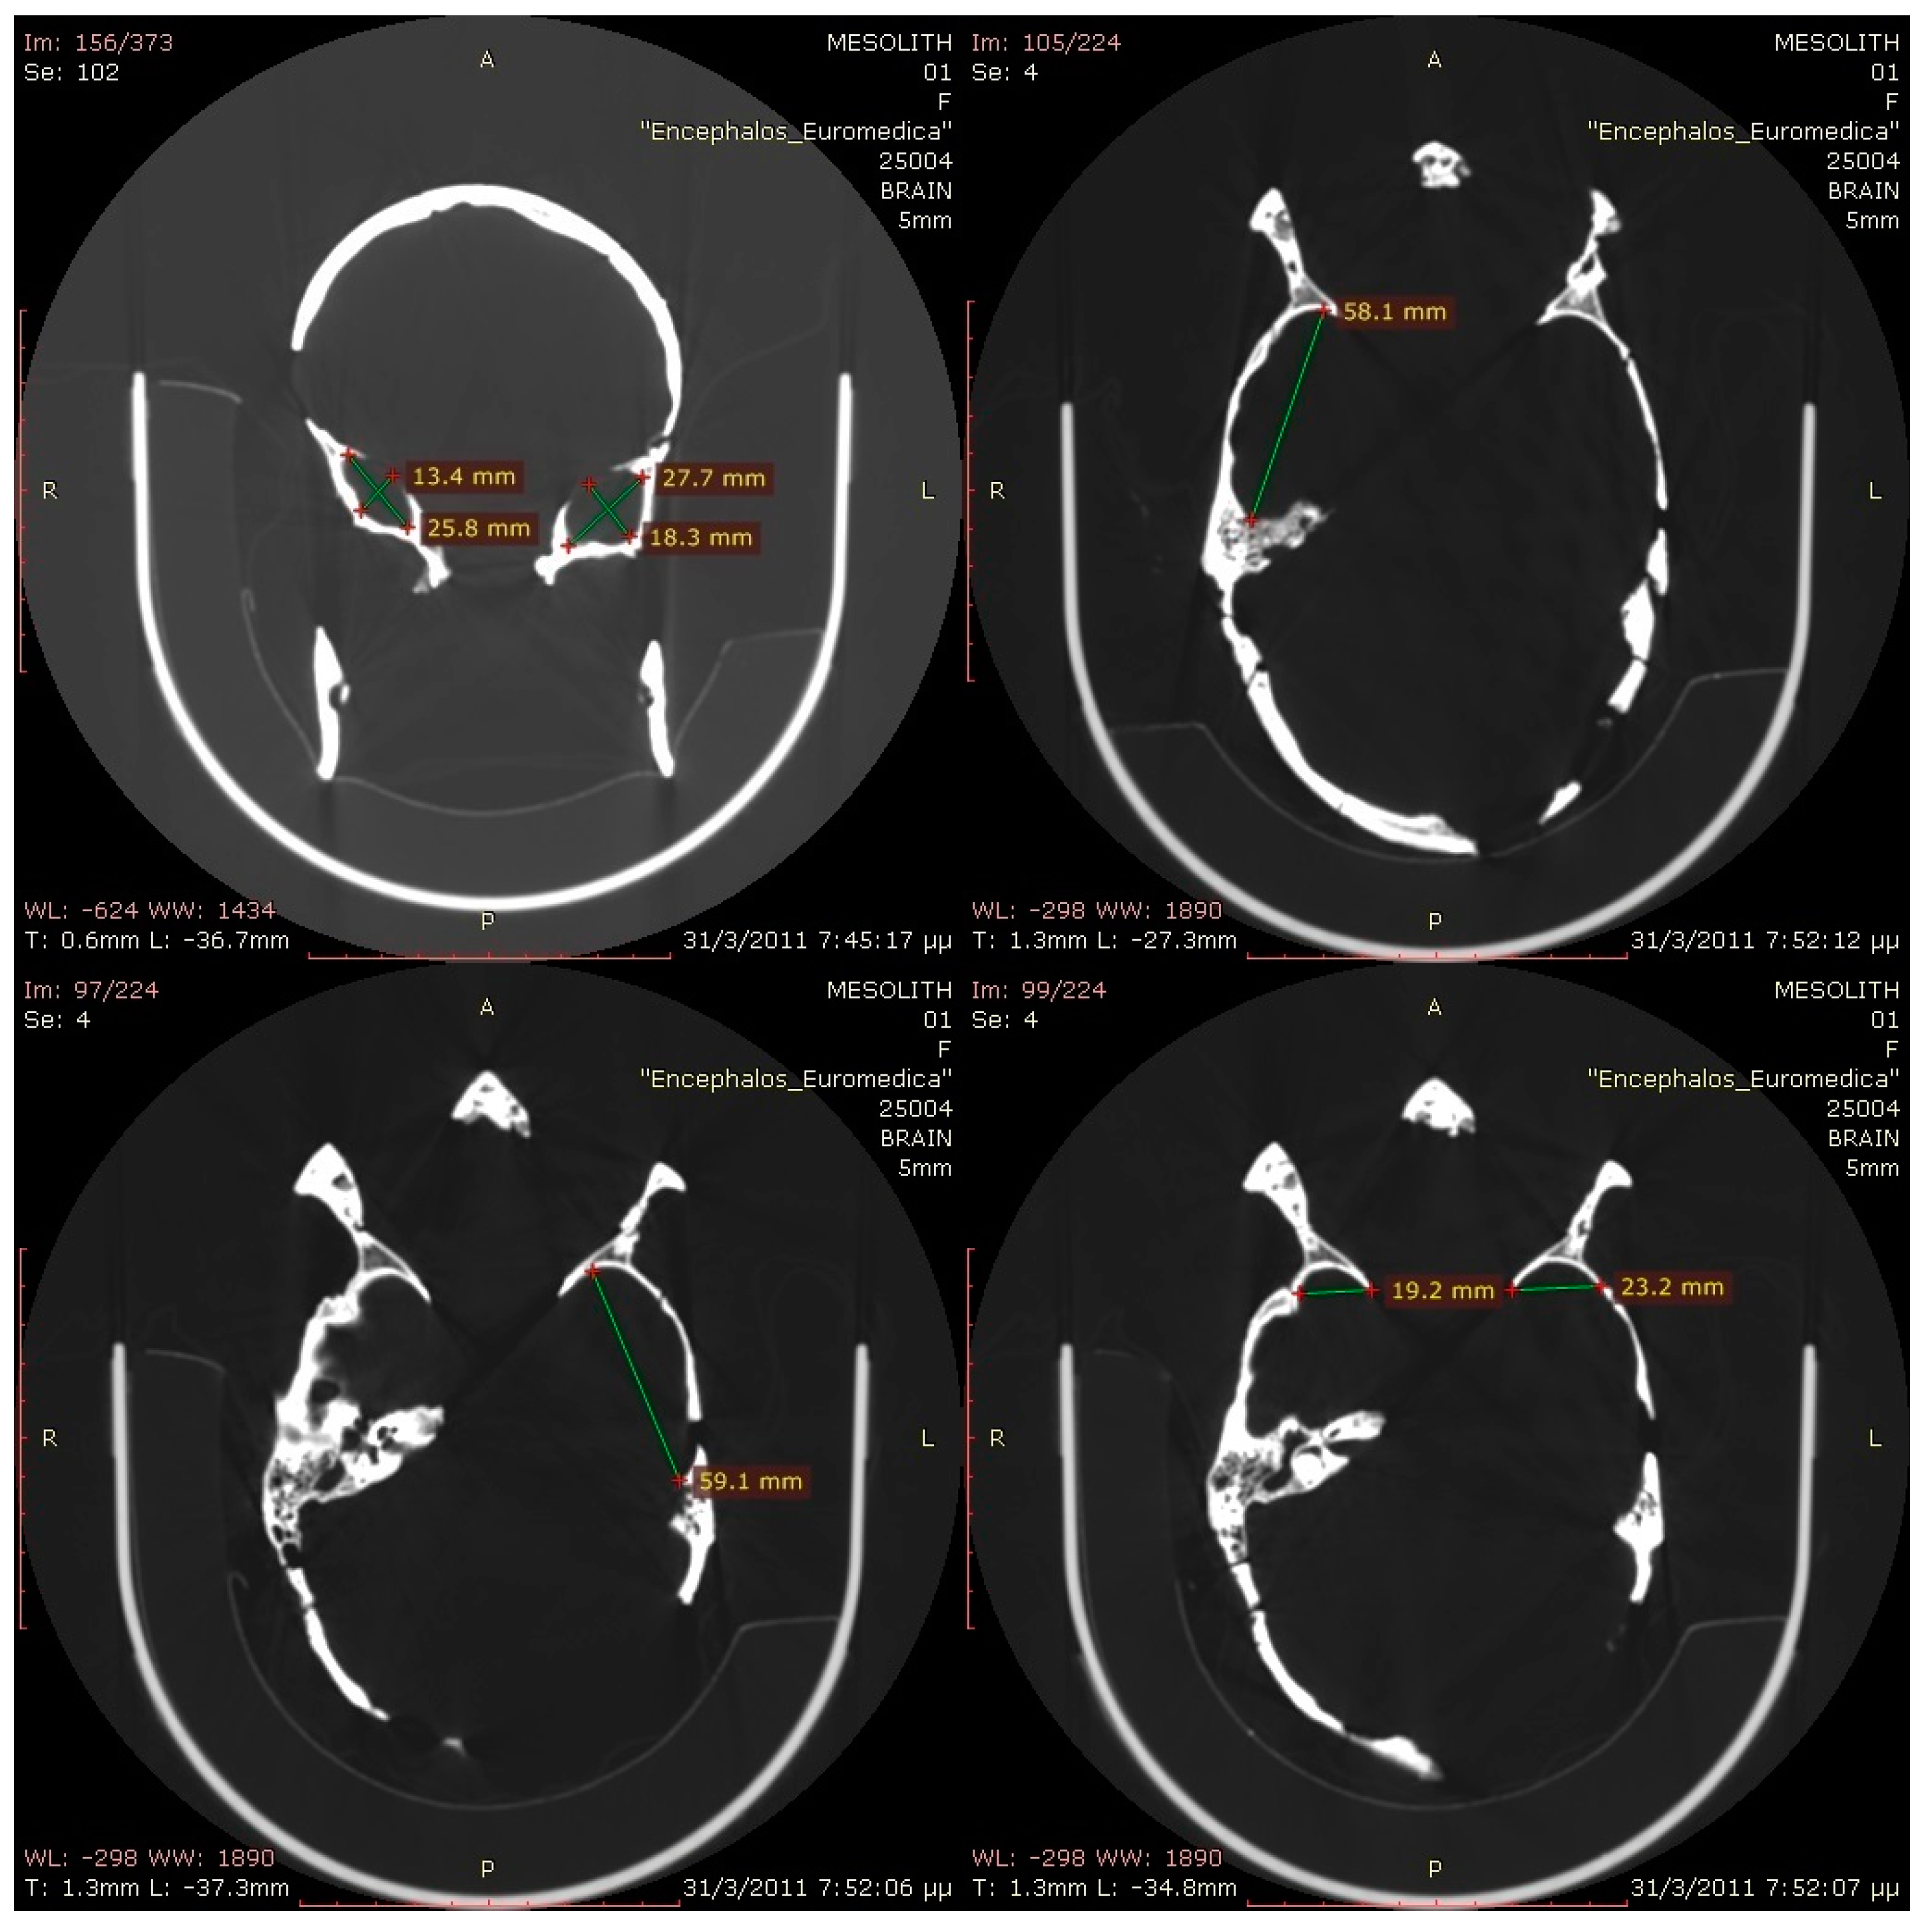

3.4. Dental Pathology

3.5. 3D Modeling